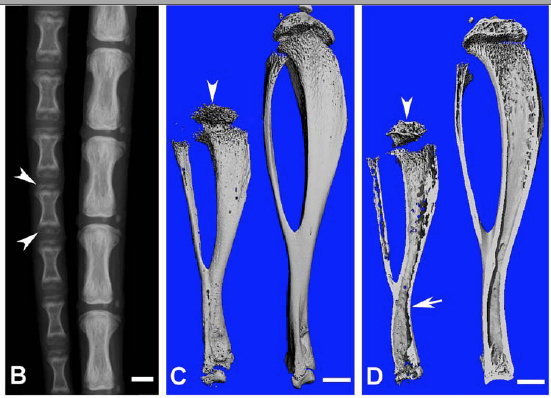

Caption Bone defects in the 6-week-old Fam20ctm1.1Cqi/Fam20ctm1.1Cqi Edil3Tg(Sox2-cre)1Amc/0 mice revealed by X-ray and histology. (B) Plain X-ray of the tail of mutant mice (left) showed hypomineralization; shorter length, and underdeveloped secondary ossification centers (arrowheads), compared with the wild-type (WT) littermates (right). (C,D) Micro-CT analyses. The tibia of the mutant mice (left) showed shorter length, thinner cortical bone (arrow), more porous areas on both the outer and inner surfaces (indicating more hypomineralized areas) and smaller secondary ossification centers (arrowheads), compared with their WT littermates (right). Scale bars: 1 mm in B-D.